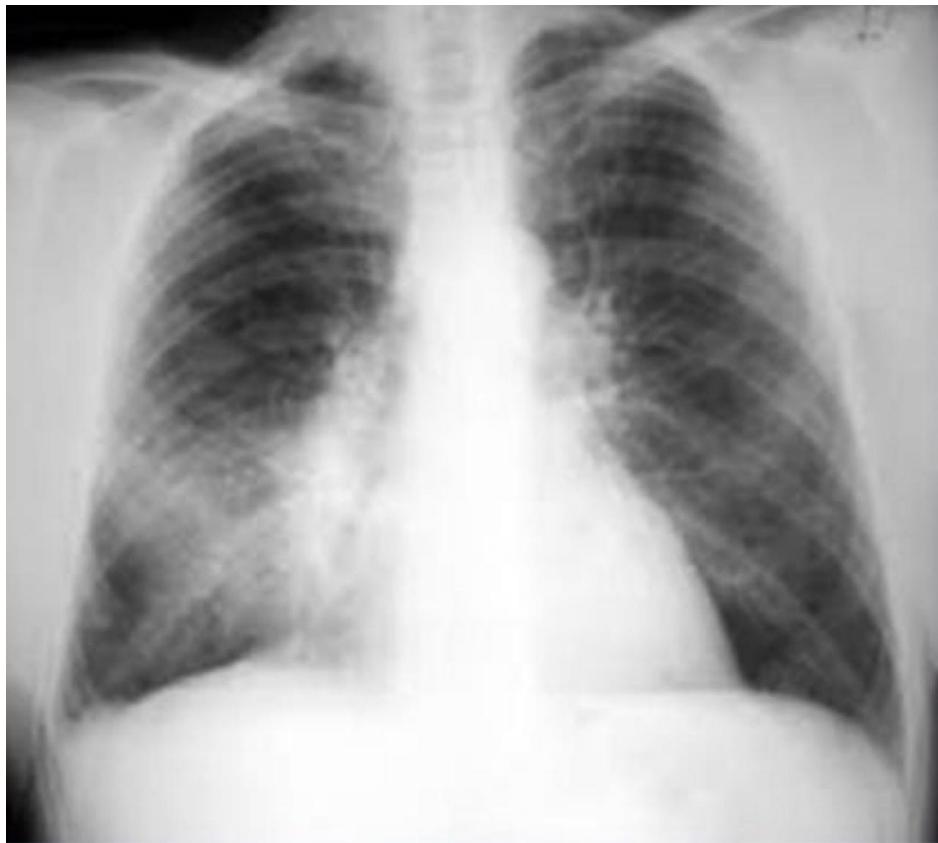

Chest X-ray: Pneumonia

- Finding: Right lower lobe consolidation.